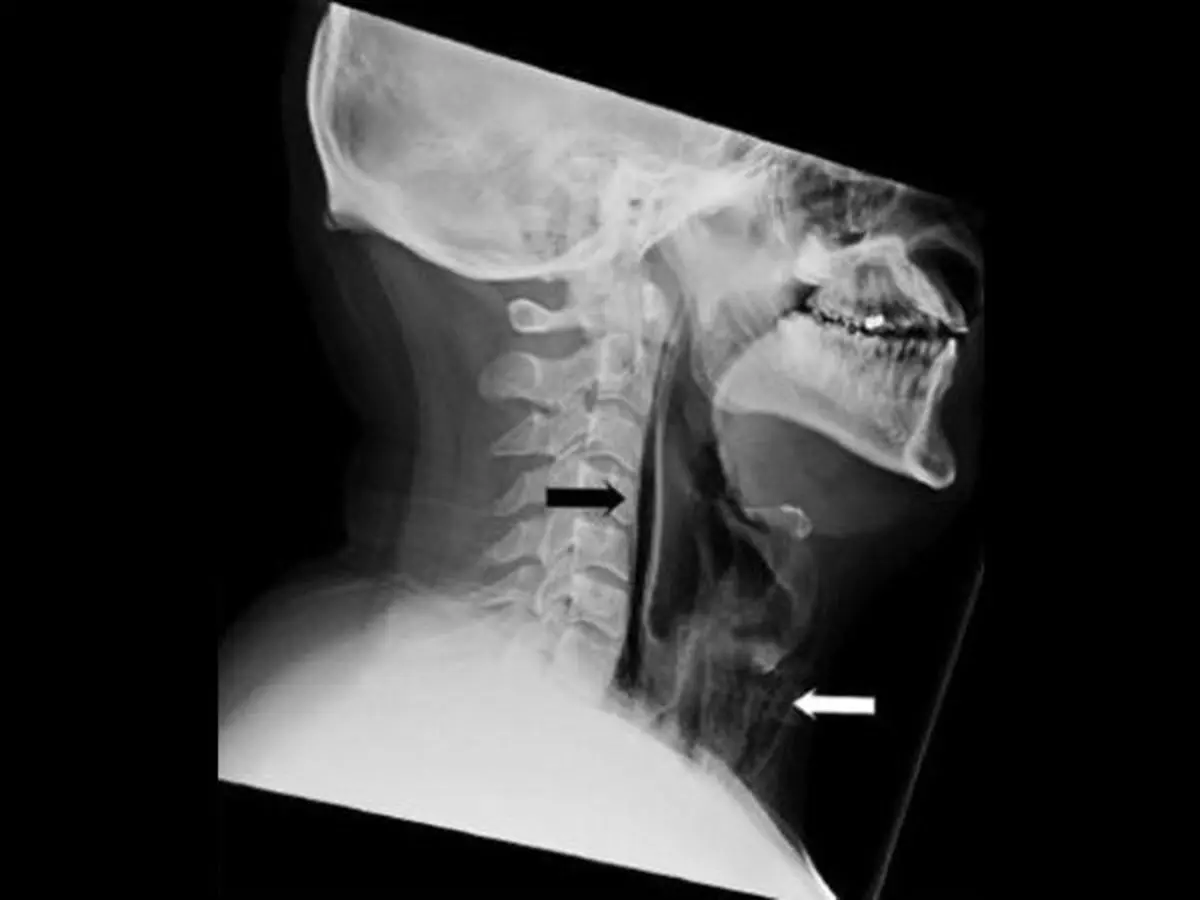

تصویربرداری‌های پزشکی (نمای فوق)، فرضیه پزشکان را تأیید کرد و از وجود رگه‌های هوا در منطقه رتروفارنژال و آمفیزم گسترده در بخش جلویی گردن پرده برداشت. به بیان ساده‌تر، این بیمار که تلاش می‌کرد جلوی عطسه کردن خودش را بگیرد، حفره کوچکی در گلوی خود ایجاد کرد.